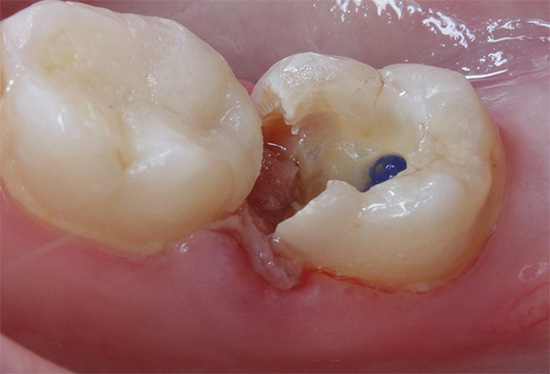

A foto abaixo mostra a polpa removida do dente: